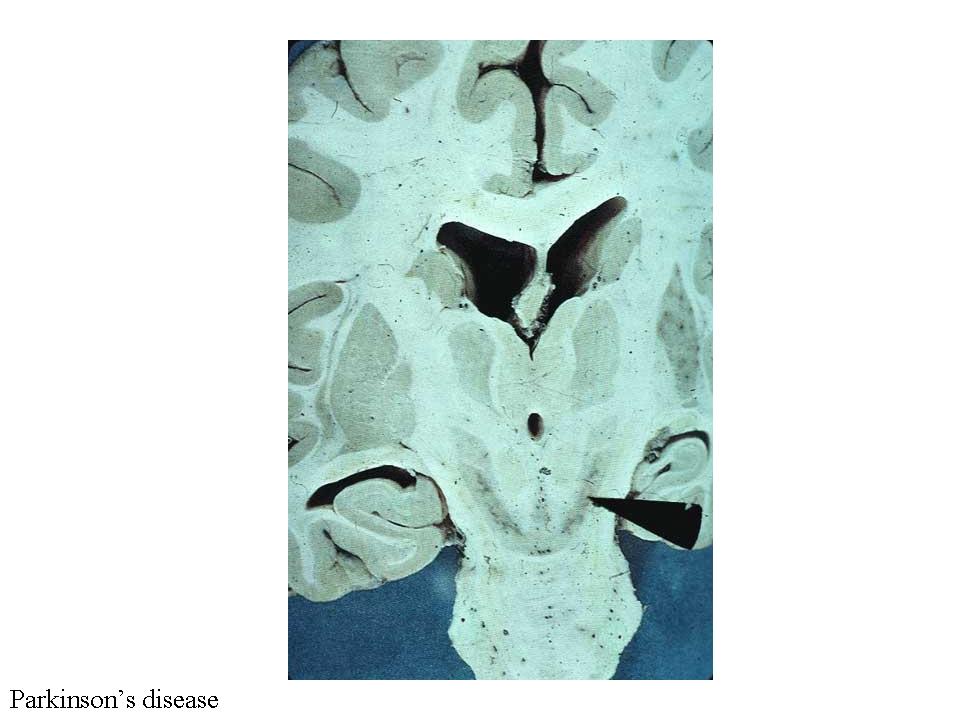

The Discovery of the Role of the

Substantia Nigra in PD...